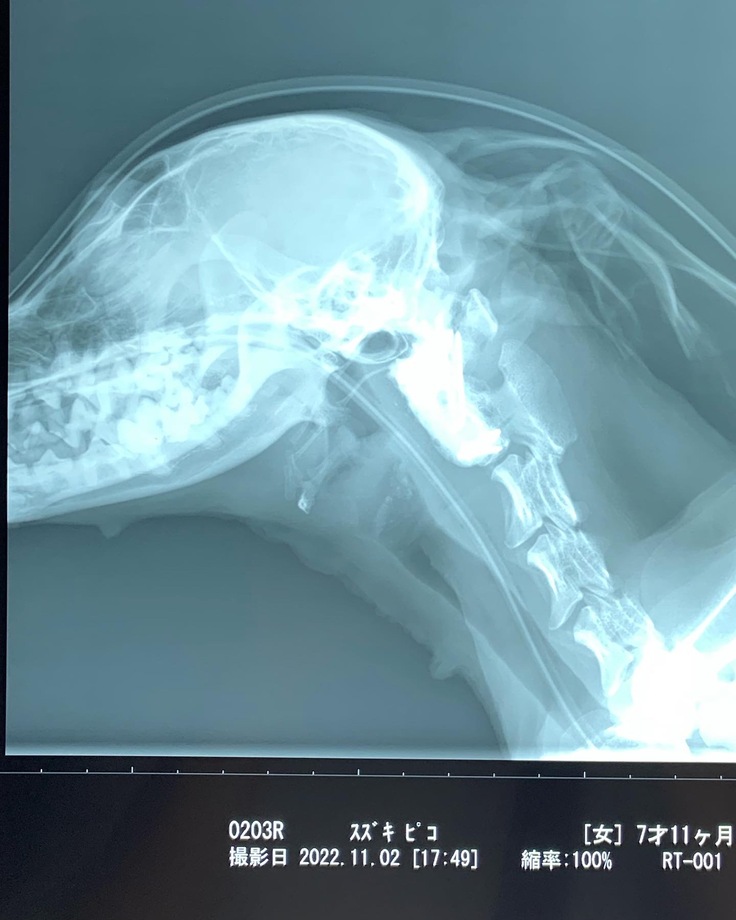

レントゲン、CT、MRIを撮ることに。

先天性の環軸亜脱臼である事が判明しました。

首の骨が脱臼しズレてしまい

脊髄を圧迫している状況

⬛︎レントゲン写真

骨が脱臼によりズレており脊髄を圧迫

⬛︎簡易の首保護のテーピングをする姿